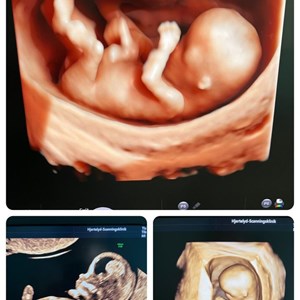

Når en 3D scanning bliver en magisk lille stund for den ventende familie 💞 Denne lille p...

Et spørgsmål jeg tit svarer på : ' Hvornår er det bedst at komme til 3D/4D scanning ?' �...